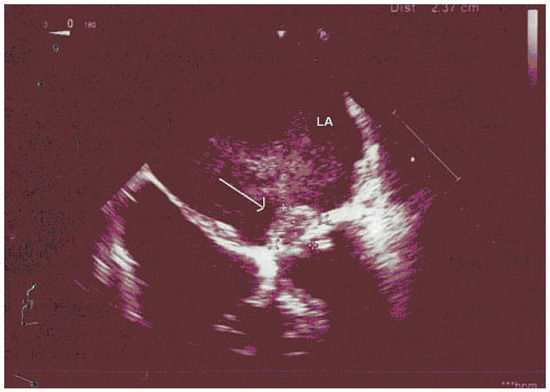

Primary Left Atrial Angiosarcoma Determining Severe Mitral Valve Stenosis

by Natalia Pavone, Vasileios Tsiopoulos, Riccardo Marano, Mariangela Novello and Mario Gaudino

Primary cardiac tumours are a rare pathogical entity. In the vast majority of cases these tumours are benign [1,2]; among malignant histotypes, angiosarcoma is the most common, representing 15–35% of all cardiac tumours [2,3]. Primary cardiac angiosarcomas usually arise from the right atrium [...] Read more.

Primary cardiac tumours are a rare pathogical entity. In the vast majority of cases these tumours are benign [1,2]; among malignant histotypes, angiosarcoma is the most common, representing 15–35% of all cardiac tumours [2,3]. Primary cardiac angiosarcomas usually arise from the right atrium or the pericardium; they typically occur in the third to fifth decade of life and are two to three times more frequent in males. We report a case of primary angiosarcoma arising from the left atrium in a female patient who had already undergone mitral valve repair. Full article